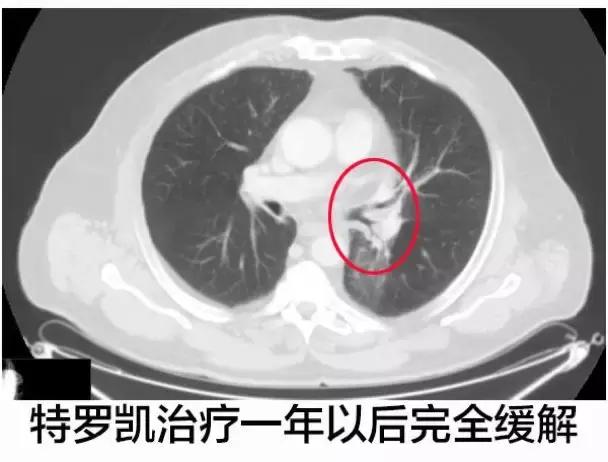

在最后一次CT影像学扫描,左肺下叶导致呼吸困难的区域还能辨识的出来,但是实体肿瘤几乎不见了,特罗凯治疗1年之后达到了完全的缓解。

研究者对患者的穿刺样本做了FISH检测,也没有发现存在EGFR基因的扩增,特罗凯治疗期间唯一的不良事件是一级皮疹,这种很早期发生的皮疹,在4周后通过局部治疗后退化,截止文章发布时病人仍在进行治疗,没有复发的迹象。